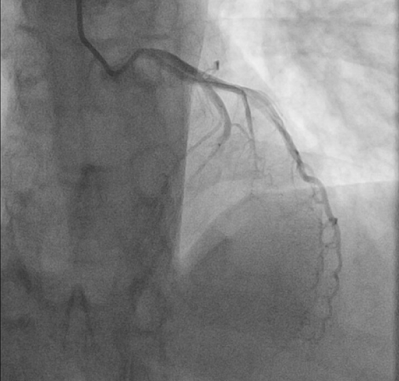

So we're concerned about the ECG - How did the patient do? Well, although the cardiac team was immediately activated, there were issues with moving to the cath lab directly.

Fortunately, the patient was able to soon proceed to the cath lab, now only reporting 1/10 chest pain. Given the improved symptoms and a "normal" ECG (followed by a "normal-er" ECG), one might expect the angiography to find only a minor or partial obstruction.

Nope.

Angiography showed a TIMI 0 lesion in the mid-LAD. Following placement of 2 stents, TIMI 3 flow was restored.